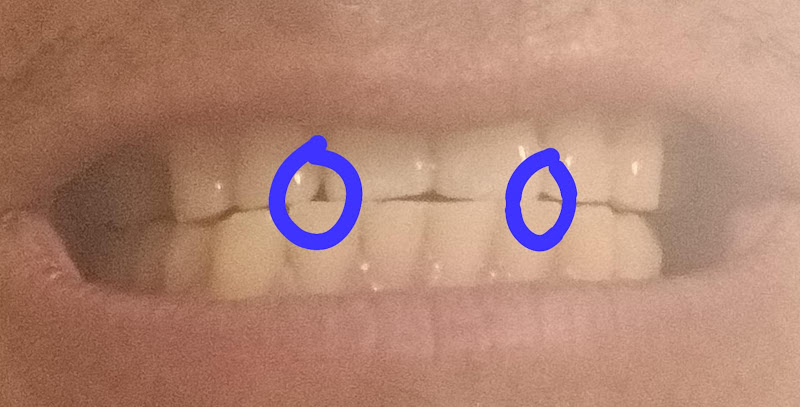

Fotos de Prosonrisas San Cristóbal